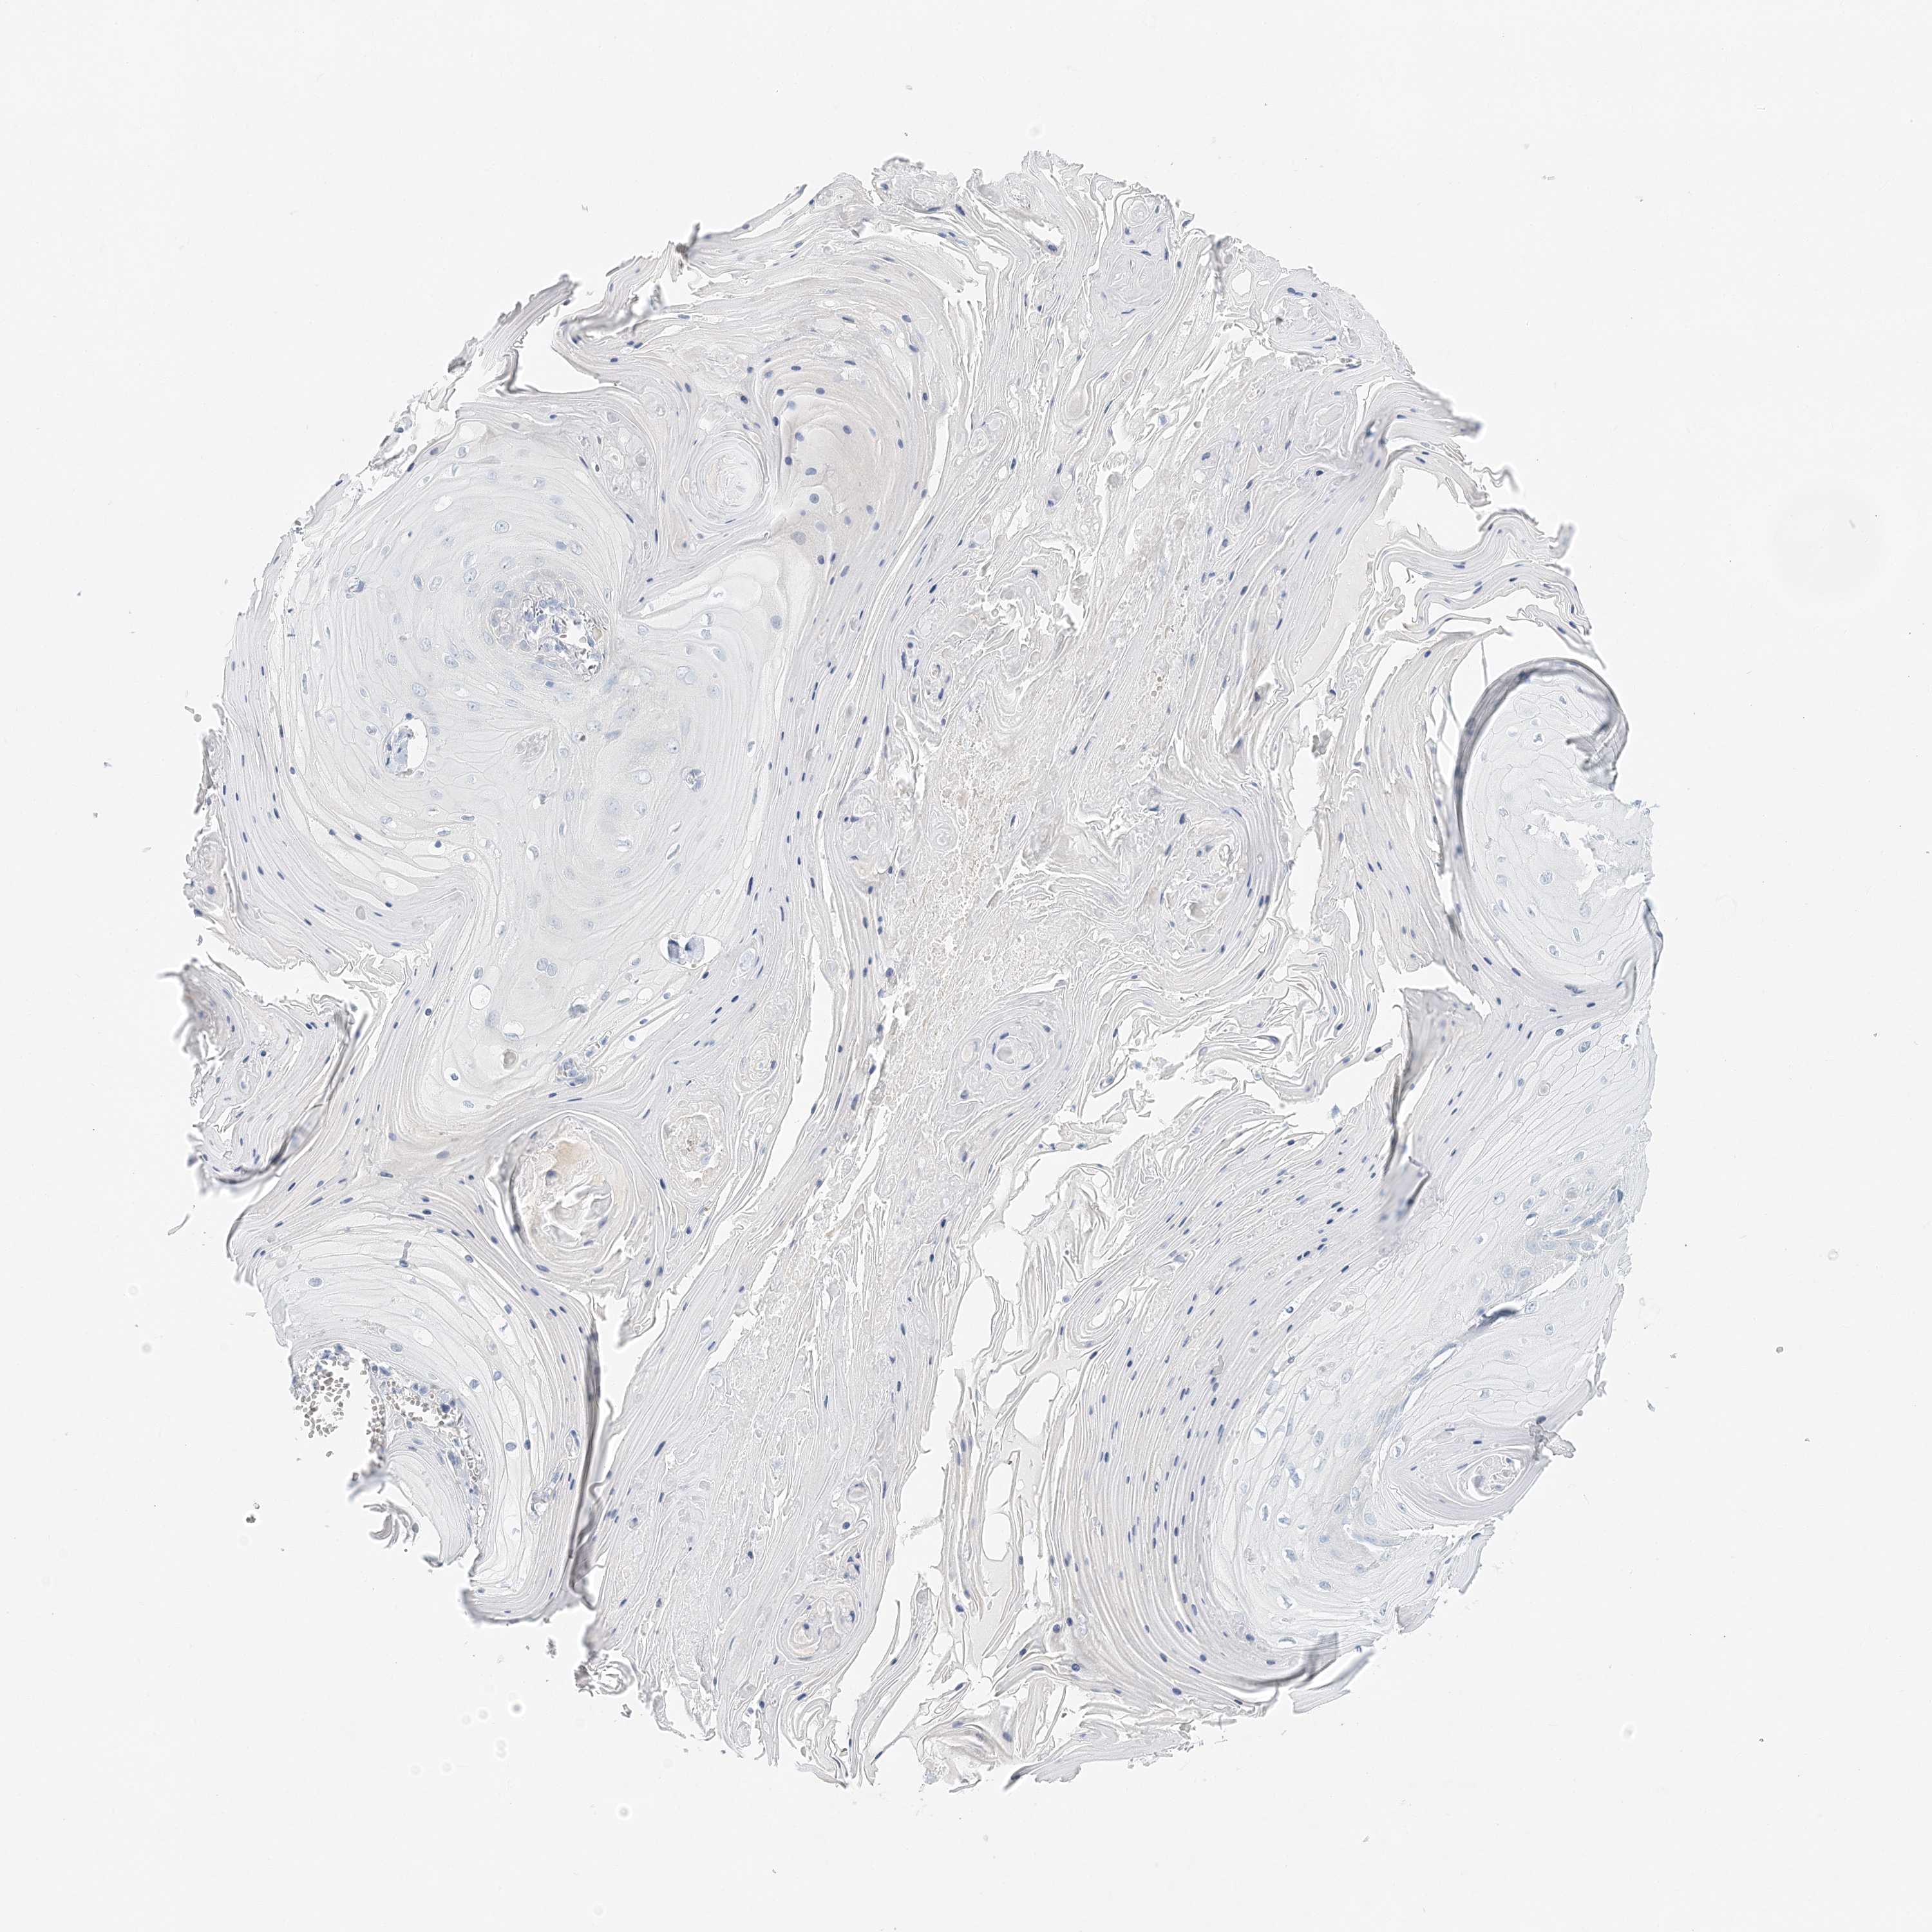

Basal cell and squamous cell cancer

SKIN CANCER - Protein expressioni

A mouse-over function shows sample information and annotation data. Click on an image to view it in a full screen mode. Samples can be filtered based on level of antibody staining by selecting one or several of the following categories: high, medium, low and not detected. The assay and annotation is described here.

Antibody stainingi

Antibody staining in the annotated cell types in the current human tissue is reported as not detected, low, medium, or high, based on conventional immunohistochemistry profiling in selected tissues. This score is based on the combination of the staining intensity and fraction of stained cells.

Each image is clickable and will lead to virtual microscopy that enables deeper exploration of all samples and also displays staining intensity scores, fraction scores and subcellular localization as well as patient and tissue information for each sample.

Antibody HPA035675

Squamous cell carcinoma, metastatic, NOS